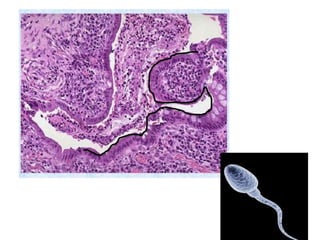

The document summarizes key aspects of liver and gallbladder anatomy and histology. It notes that hepatocytes in the liver have abundant mitochondria and are surrounded by peri-sinusoidal spaces filled with microvilli. The gallbladder stores and concentrates bile produced by the liver through absorption and secretion. The gallbladder can become inflamed or damaged due to blockage and accumulation over time.